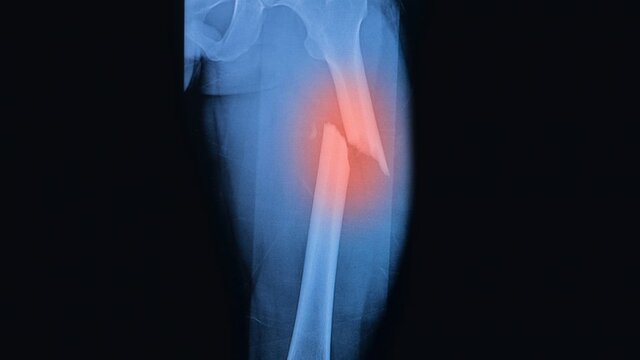

• rotura muscular total

rotura muscular total

En este caso, la rotura afecta a todo el grosor del músculo y se manifiesta con la aparición de dolor sincopal y chasquido característico. Además, se observa la depresión de la zona que ha sufrido la ruptura, produciéndose el signo del “hachazo” y la retracción del vientre del músculo roto, formando una herniación muscular por encima del “hachazo” . La incapacidad funcional es instantánea y duradera e impide la realización de cualquier ejercicio.